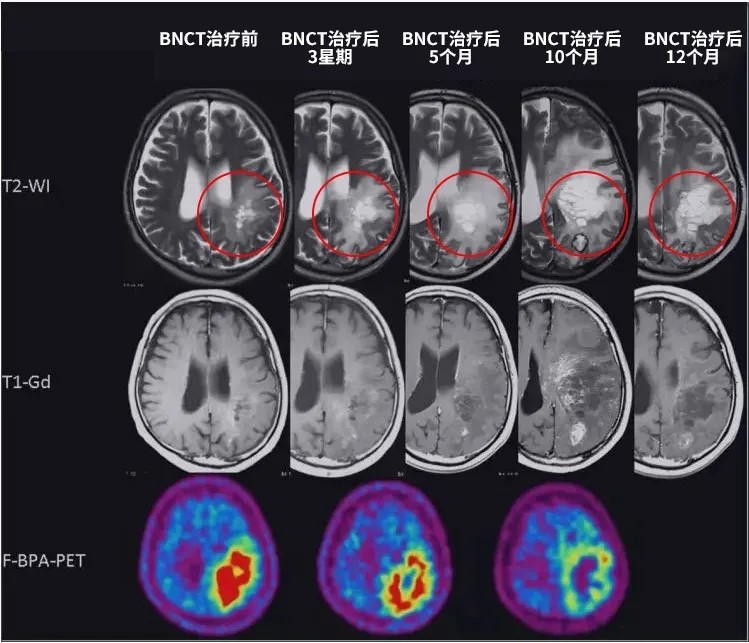

BNCT硼中子俘获如何一步步治疗脑瘤?附临床疗效汇总

BNCT治疗脑瘤。关于癌症放疗,质子治疗的前沿和先进性渐渐广为熟知。实际上,还有一种比质子更为精准、副作用更低的放疗黑科技可惠及更多癌症患者,也就是大家可能已有耳闻的硼中子俘获(BNCT)。尽管该技术早几年都处在临床试验阶段,但已有越来越多的研究证实,BNCT之于脑肿瘤及其他一些癌症的有效性。

传统放疗“杀敌一千,自损八百”,质子治疗极大提高了放疗的精准性,而BNCT的安全性则更高。BNCT所产生的α粒子和锂离子射程很短,只有一个细胞的长度,所以只“杀死”癌细胞而不损伤周围细胞组织。对于脑胶质瘤、黑色素瘤和头颈部复发肿瘤,BNCT是非常有效的放疗手段,并试治肝癌、肺癌、胰腺癌等脏器肿瘤。

BNCT治疗脑肿瘤的临床研究数据